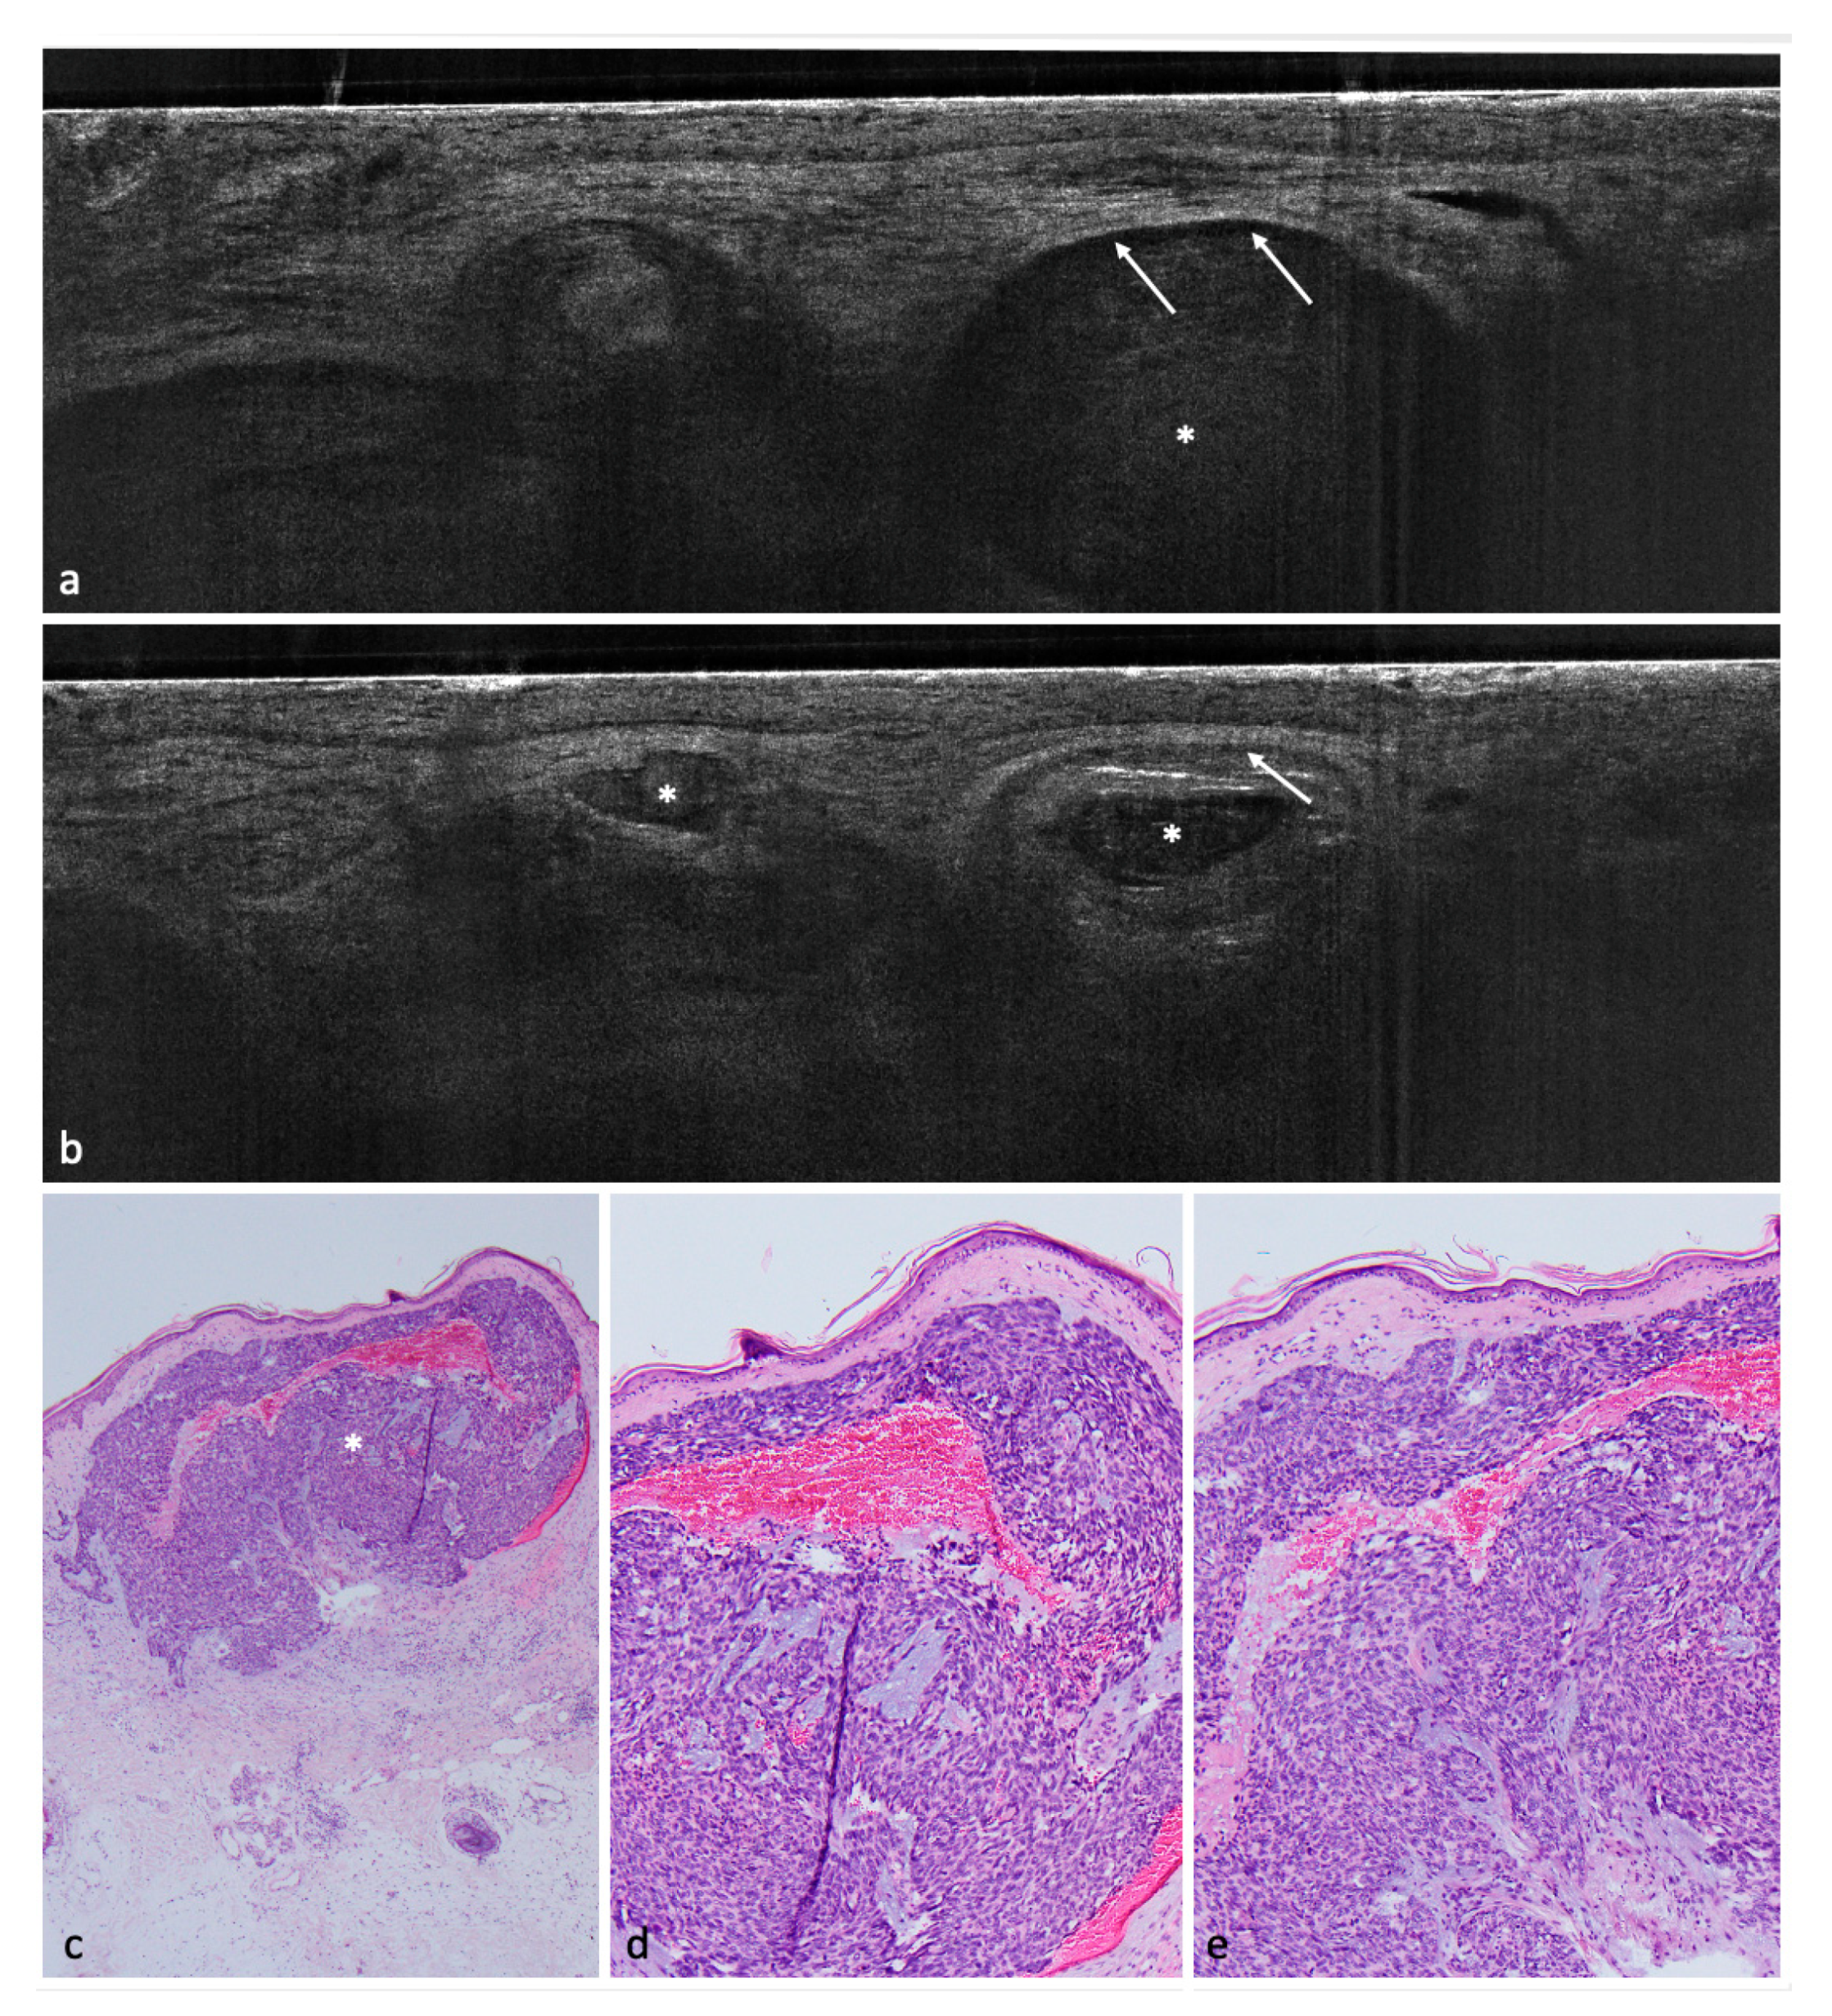

Figure 4. Molluscum contagiosum on the forehead of a 58-year-old male patient. (a) (100×) and (b) (40×): histological hematoxylin and eosin (HE)-stained sections. In histology, a cup-shaped multilobular lesion can be identified. Red arrows indicate intracytoplasmatic inclusion bodies (Henderson–Paterson bodies) which contain virus particles. (ce) LC-OCT image of the molluscum contagiosum. It shows acanthosis (white bar) and hyporeflective areas with hazy structures, which probably correspond to the Henderson–Paterson bodies (red arrow).